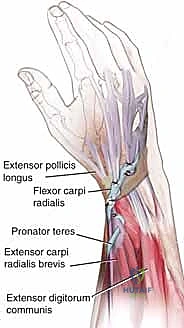

FIG 1 • Tendons on the dorsum of the hand, extensor retinaculum.